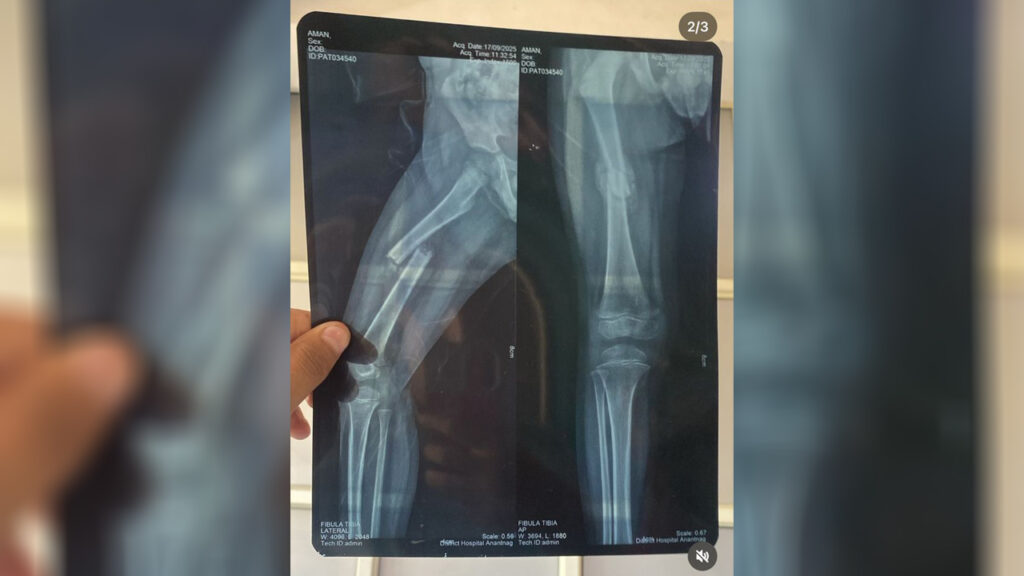

By Allah’s mercy and grace, one of our team members took the responsibility and did not wait even a moment. The boy was immediately arranged to be taken to Anantnag. There he was admitted to the hospital, prepared for surgery. Every medical expense, scan, treatment, surgery. Was pledged and covered by Miles2Smile. The boy’s mother, overwhelmed with relief, held her child’s hand tightly, as if she had been given back a part of her world.